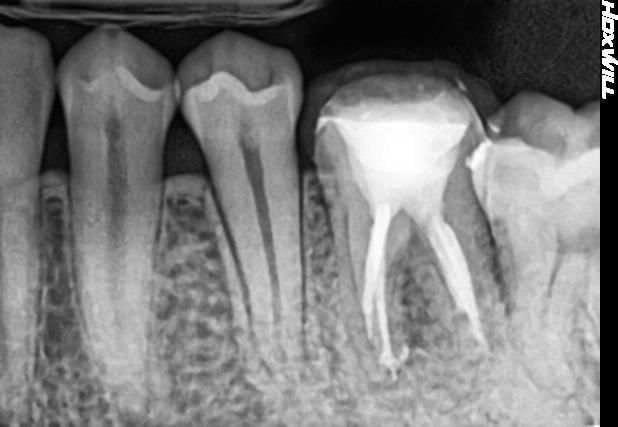

3번째 사진은 치료가 끝난 직후 치근단 사진입니다.

• 3번 째 사진